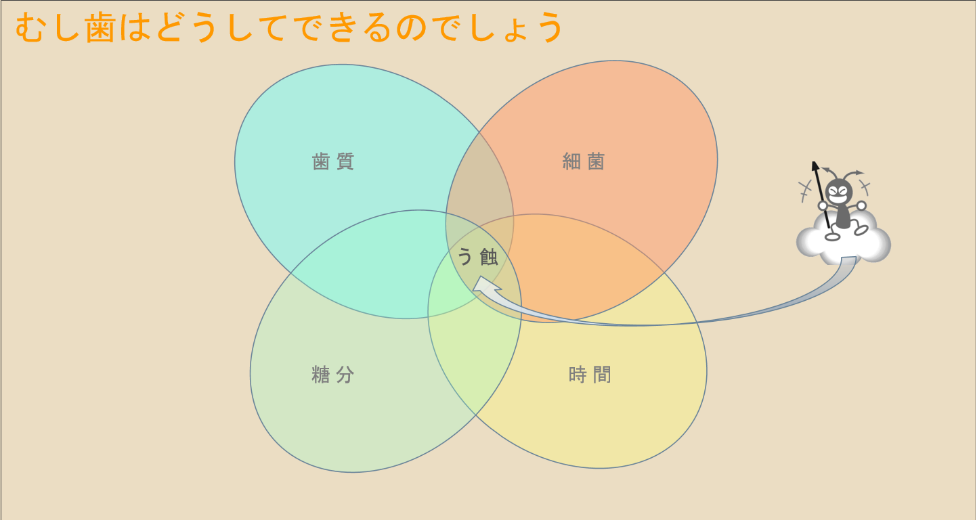

むし歯の原因